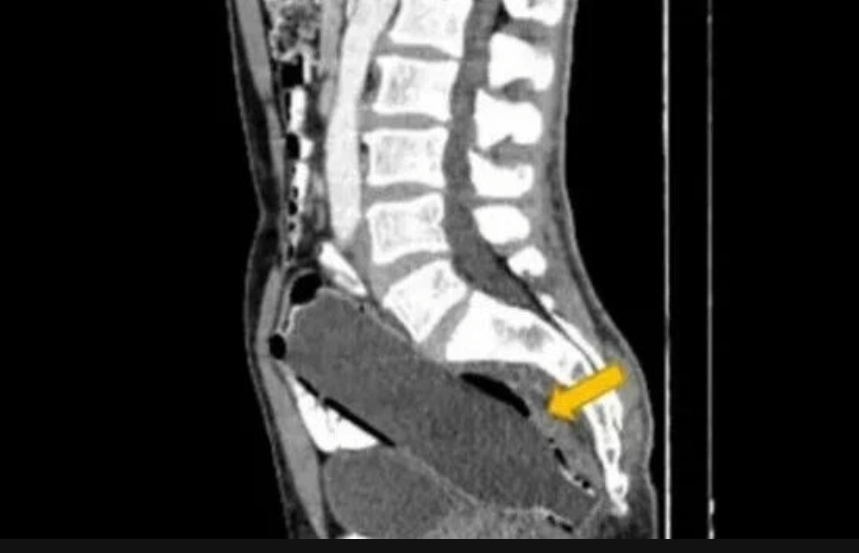

Um paciente de 50 anos chegou a um hospital iraniano acompanhado de sua esposa, contando estar sofrendo há três dias com constipação, dores no estômago e falta de apetite. Uma tomografia computadorizada mostrou que o homem tinha uma garrafa plástica de 250 ml introduzida no reto.

O objeto se encontrava a 10 milímetros da abertura do ânus, entre o reto e o cólon, mas não chegou a danificar o intestino do paciente.